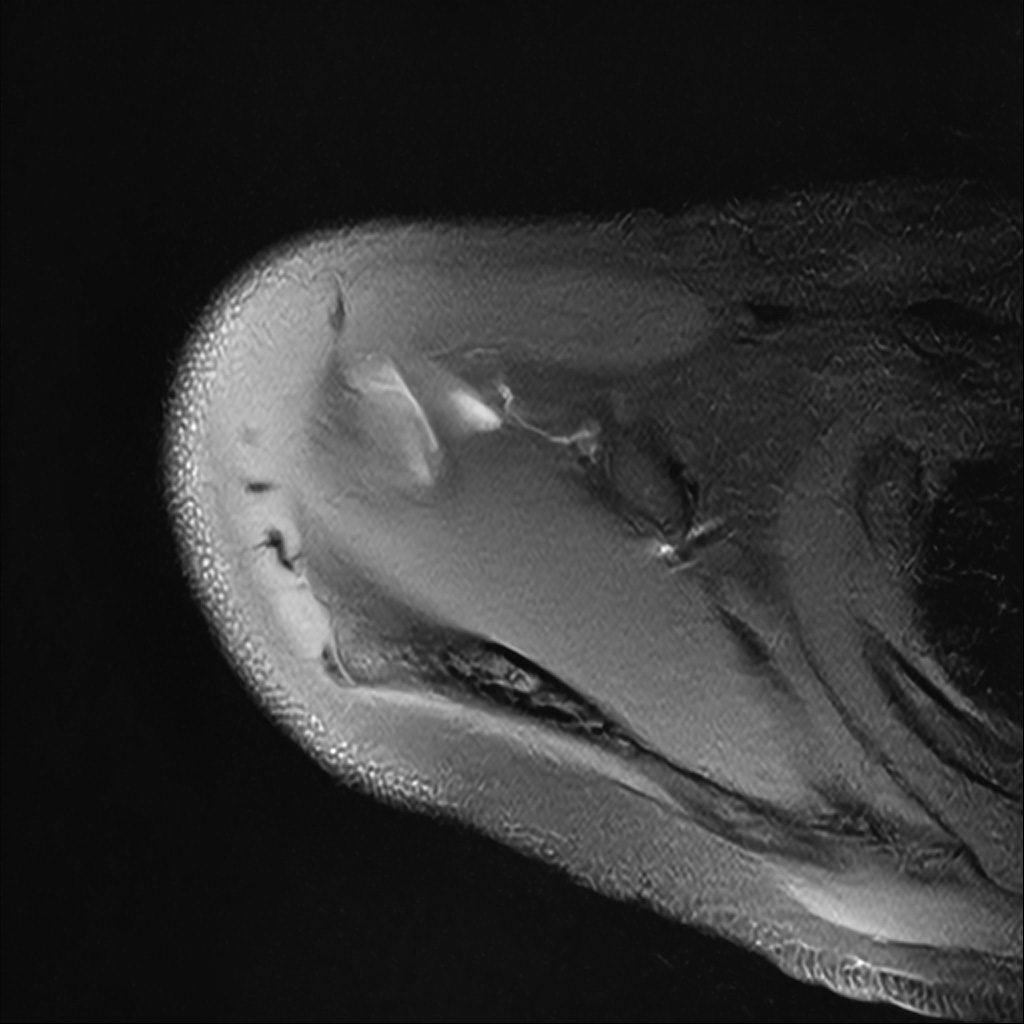

Mri 단면 영상으로 보아 어깨 관절 부위에서 이상 신호가 관찰되고 이는 관절 와순 파열의 가능성을 시사할 수 있습니다.

하지만 이영상만으로 정확한 진단은 불가능하고 정밀한 판단을 위해선 전체 시퀀스와 영상의학과 전문의의 공식판독이 필요합니다 특히 와순 파열은 위치와 동반 병변에 따라 해석이 달라집니다!